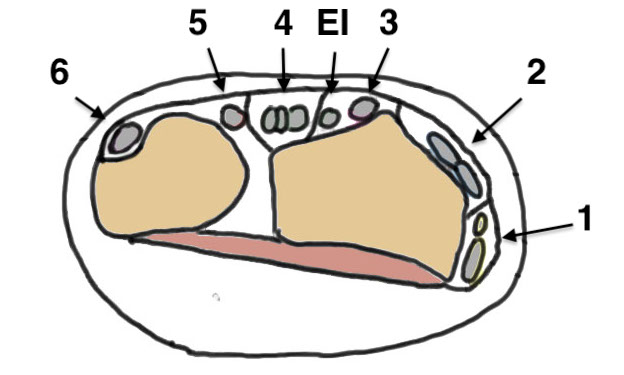

Dorsal distal radius

- 2 x half pins 4mm

- proximally between EDC and ECRB / ECRL

- bare area of radius

Metacarpal

- 2 x half pins index or second metacarpal 3 mm

- distal and proximal metaphysis

- insert at 30 degrees to prevent transfixing extensor tendon

- flex MCP to 90 degrees with when placing distal pin to avoid extensor hood